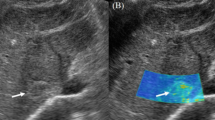

Fluctuational Imaging software analysis results were positive for “fluttering sign” in 38 hepatic hemangiomas. Figures 1, 2 and 3 shows the results for Supplementary video V1, Supplementary video V2, and Supplementary video V3, respectively.

Four cases with different results in the grayscale US videos and Fluctuational Imaging software analysis were negative on grayscale US videos and positive on Fluctuational Imaging software analysis. The different results were considered to arise from the effects of pulsation. Figure 4 shows a colored area thought to arise from an effect of the heartbeat rather than “fluttering sign” (Supplementary video V4).